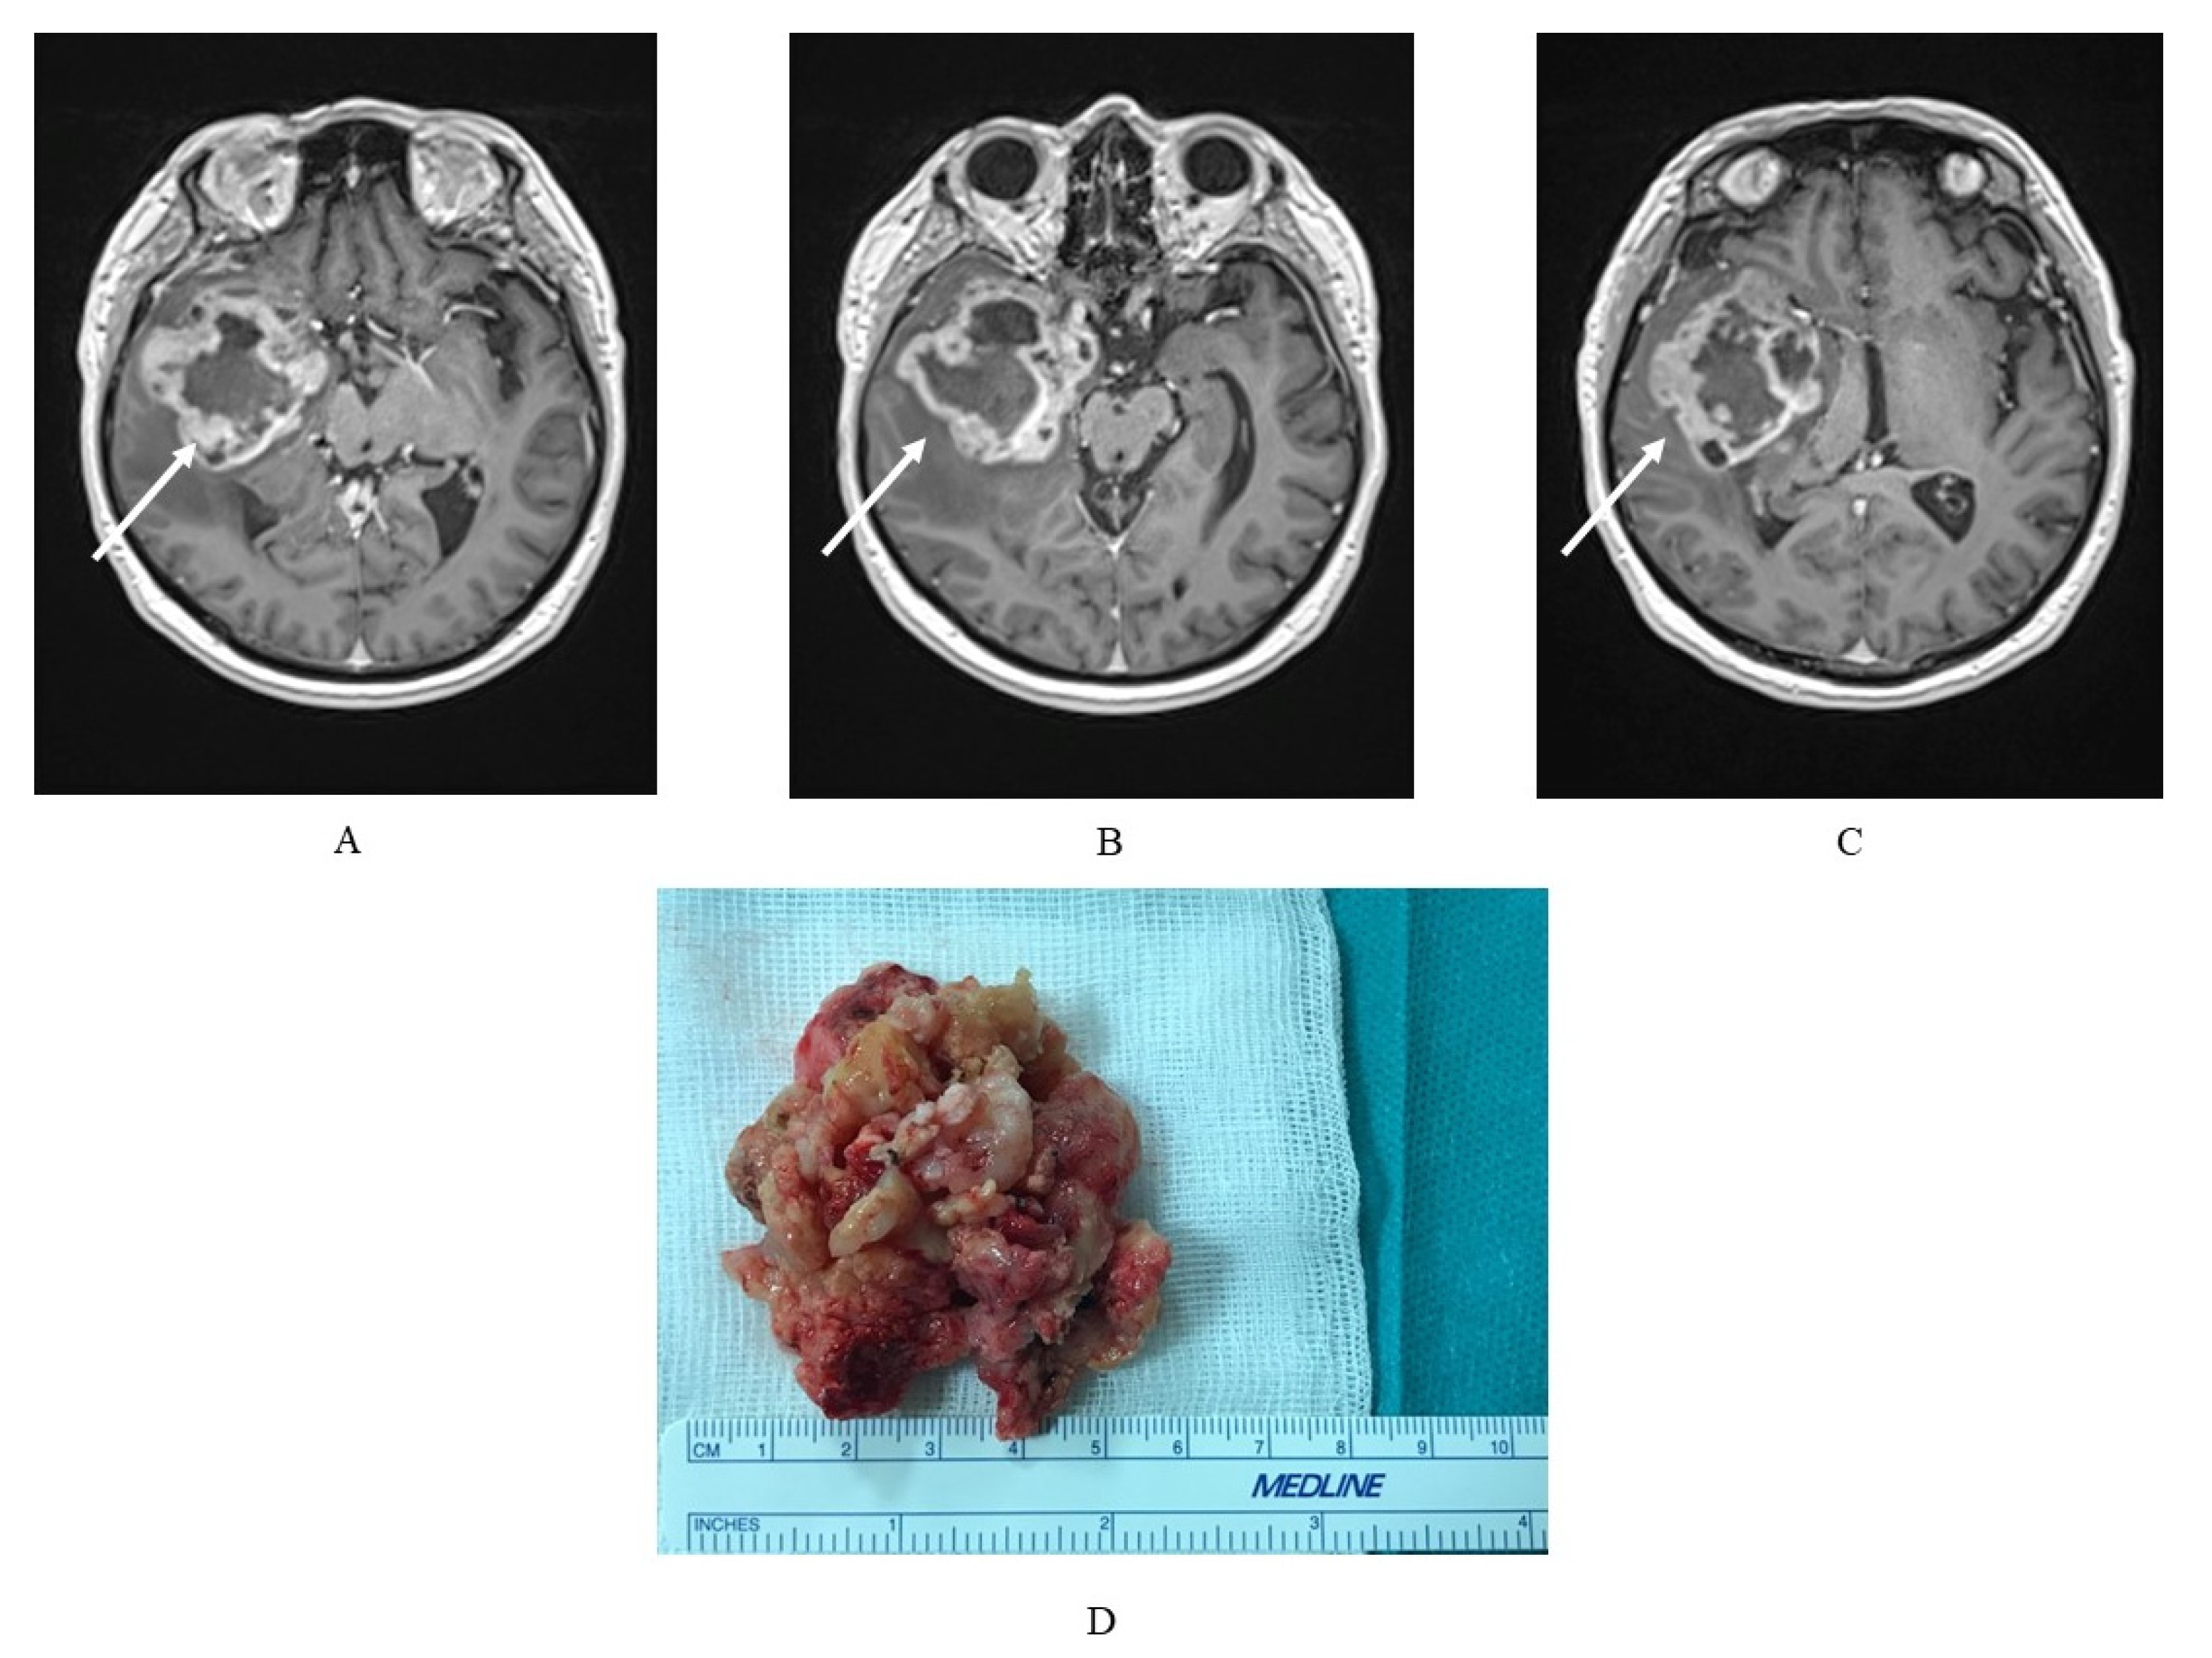

2. Characteristics of Glioblastoma Multiforme